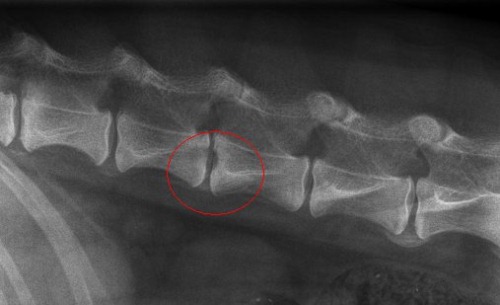

На рентгеновском снимке грыжа Шморля практически всегда распознается. Специалист может заметить незначительную вогнутость замыкательной пластинки соседних позвонков на определенных уровнях. Также видны участки остеосклероза вокруг пораженной зоны. Путать эту патологию с межпозвонковой грыжей или другими заболеваниями невозможно, так как при рассматриваемом нарушении не происходит разрушения фиброзного кольца, что видно на рентгенограмме.

Рентгеновский снимок позволяет выявить грыжу Шморля даже у пожилых людей. Врач может наблюдать вдавливания верхней и нижней замыкательных пластинок одного сегмента позвоночника. Эти изменения могут служить основанием для точной диагностики.